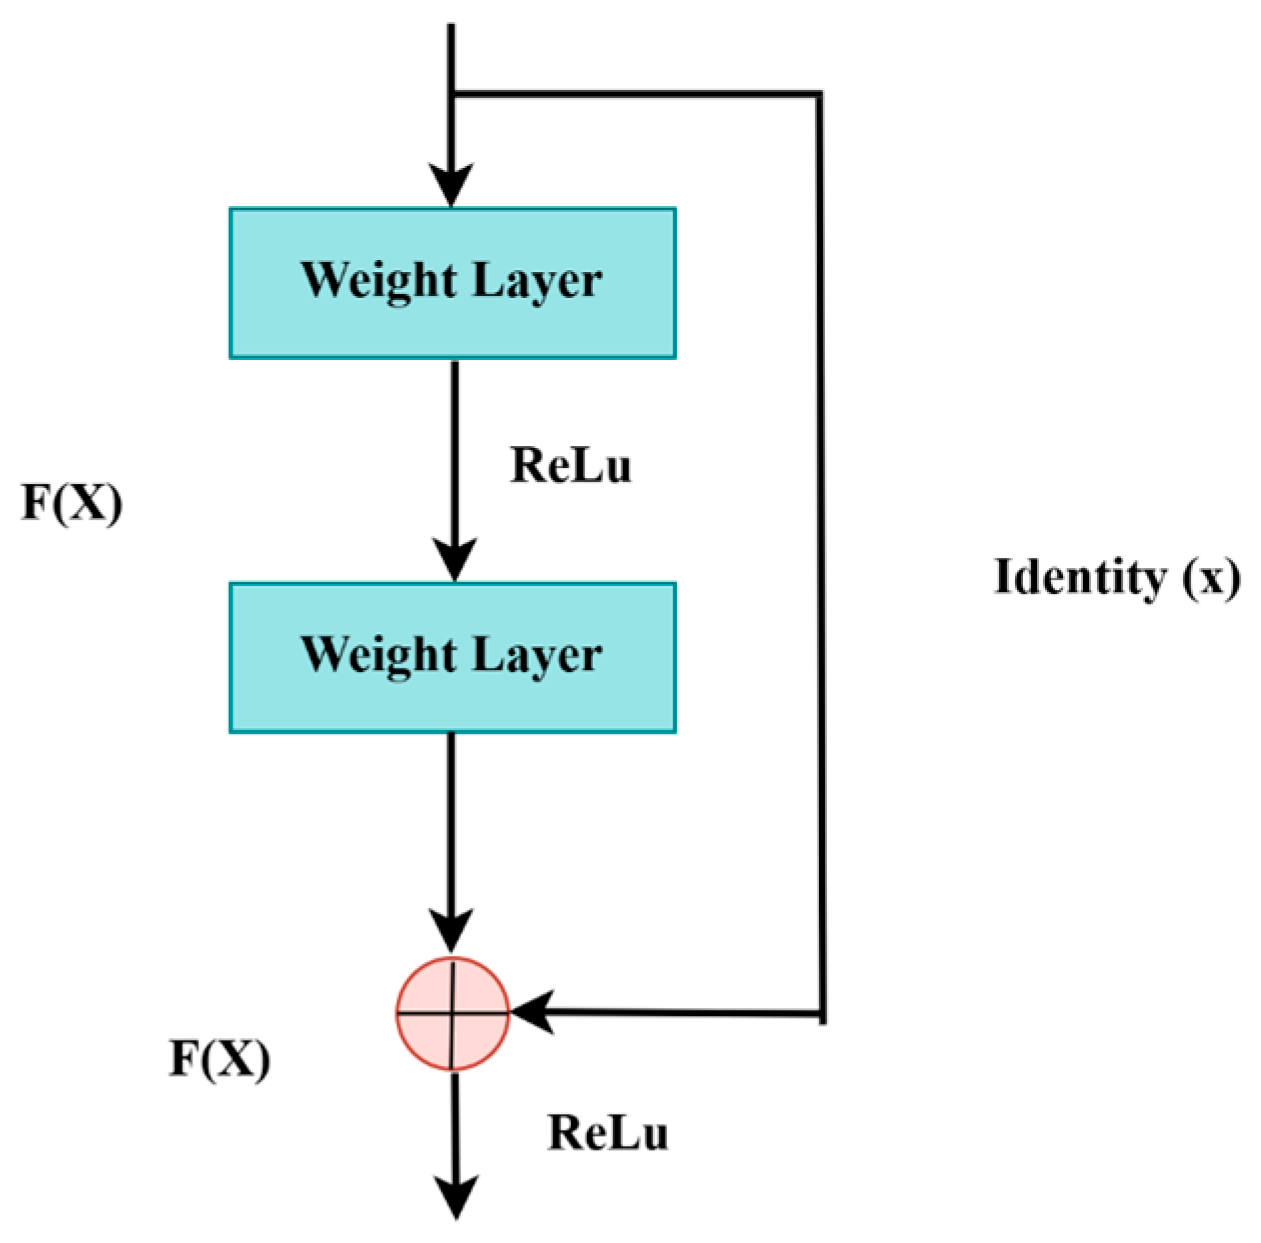

3.3.1. Pre-Trained Encoder

3.6. ResNet-50 + U-Net

3.6.4. ResNet-50 Backbone